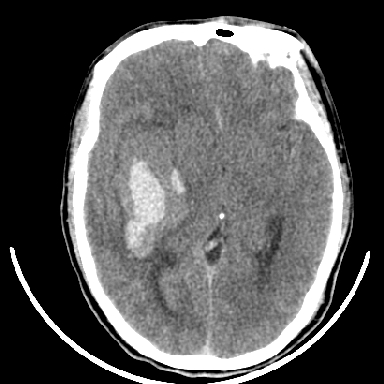

术中抽出40ml陈旧血液,血肿底部似见一条索血管影

胶质母细胞瘤可能性大

瘤卒中

支持胶质瘤并出血